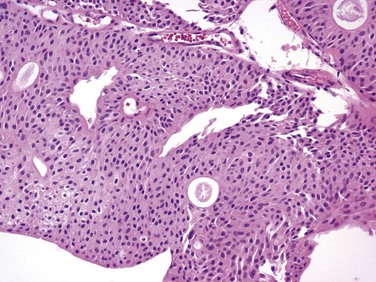

Figure 81–3 Ta low-grade tumor (×40). Cells are relatively normal but exhibit irregularity and some nuclear differentiation.

CIS lesions are composed of severely dysplastic urothelium. Microscopically, the slide will demonstrate disorderly histology with nuclear atypia characteristic of high-grade malignancy; denudement of some or all of the mucosa due to loss of cellular cohesion sometimes complicates interpretation. A pathology report read as dysplasia or atypia can create confusion. Most pathologists consider mild examples of these entities to be benign. However, lesions interpreted as severe dysplasia or severe atypia are regarded as being the same entity as CIS (Epstein et al, 1998). Again, unambiguous communication between pathologist and urologist can minimize the risk for misinterpretation.